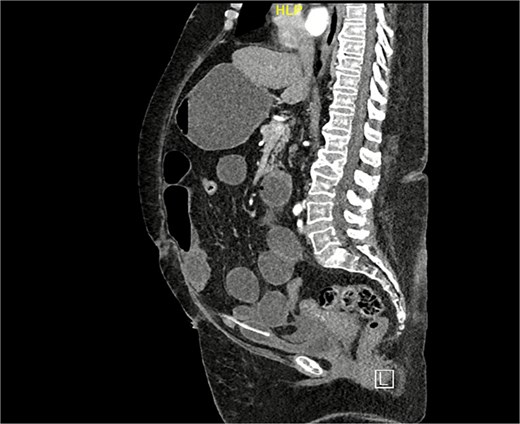

A computed tomography (CT) scan of the abdomen and pelvis was performed for further evaluation. The coronal view demonstrated a markedly distended stomach, mesenteric fat stranding with a small amount of free fluid, along with bowel dilation involving the mid and proximal small bowel loops (measuring up to 4 cm) with a transition zone at the site of bowel twisting over the suprapubic catheter (Fig. 1). On the sagittal view, the suprapubic catheter was seen positioned correctly within the bladder (Fig. 2). The bowel demonstrated normal enhancement, with no evidence of wall thickening, pneumatosis intestinalis, or pneumoperitoneum.

CT scan sagittal view: Demonstrating suprapubic catheter in its appropriate position within the bladder.